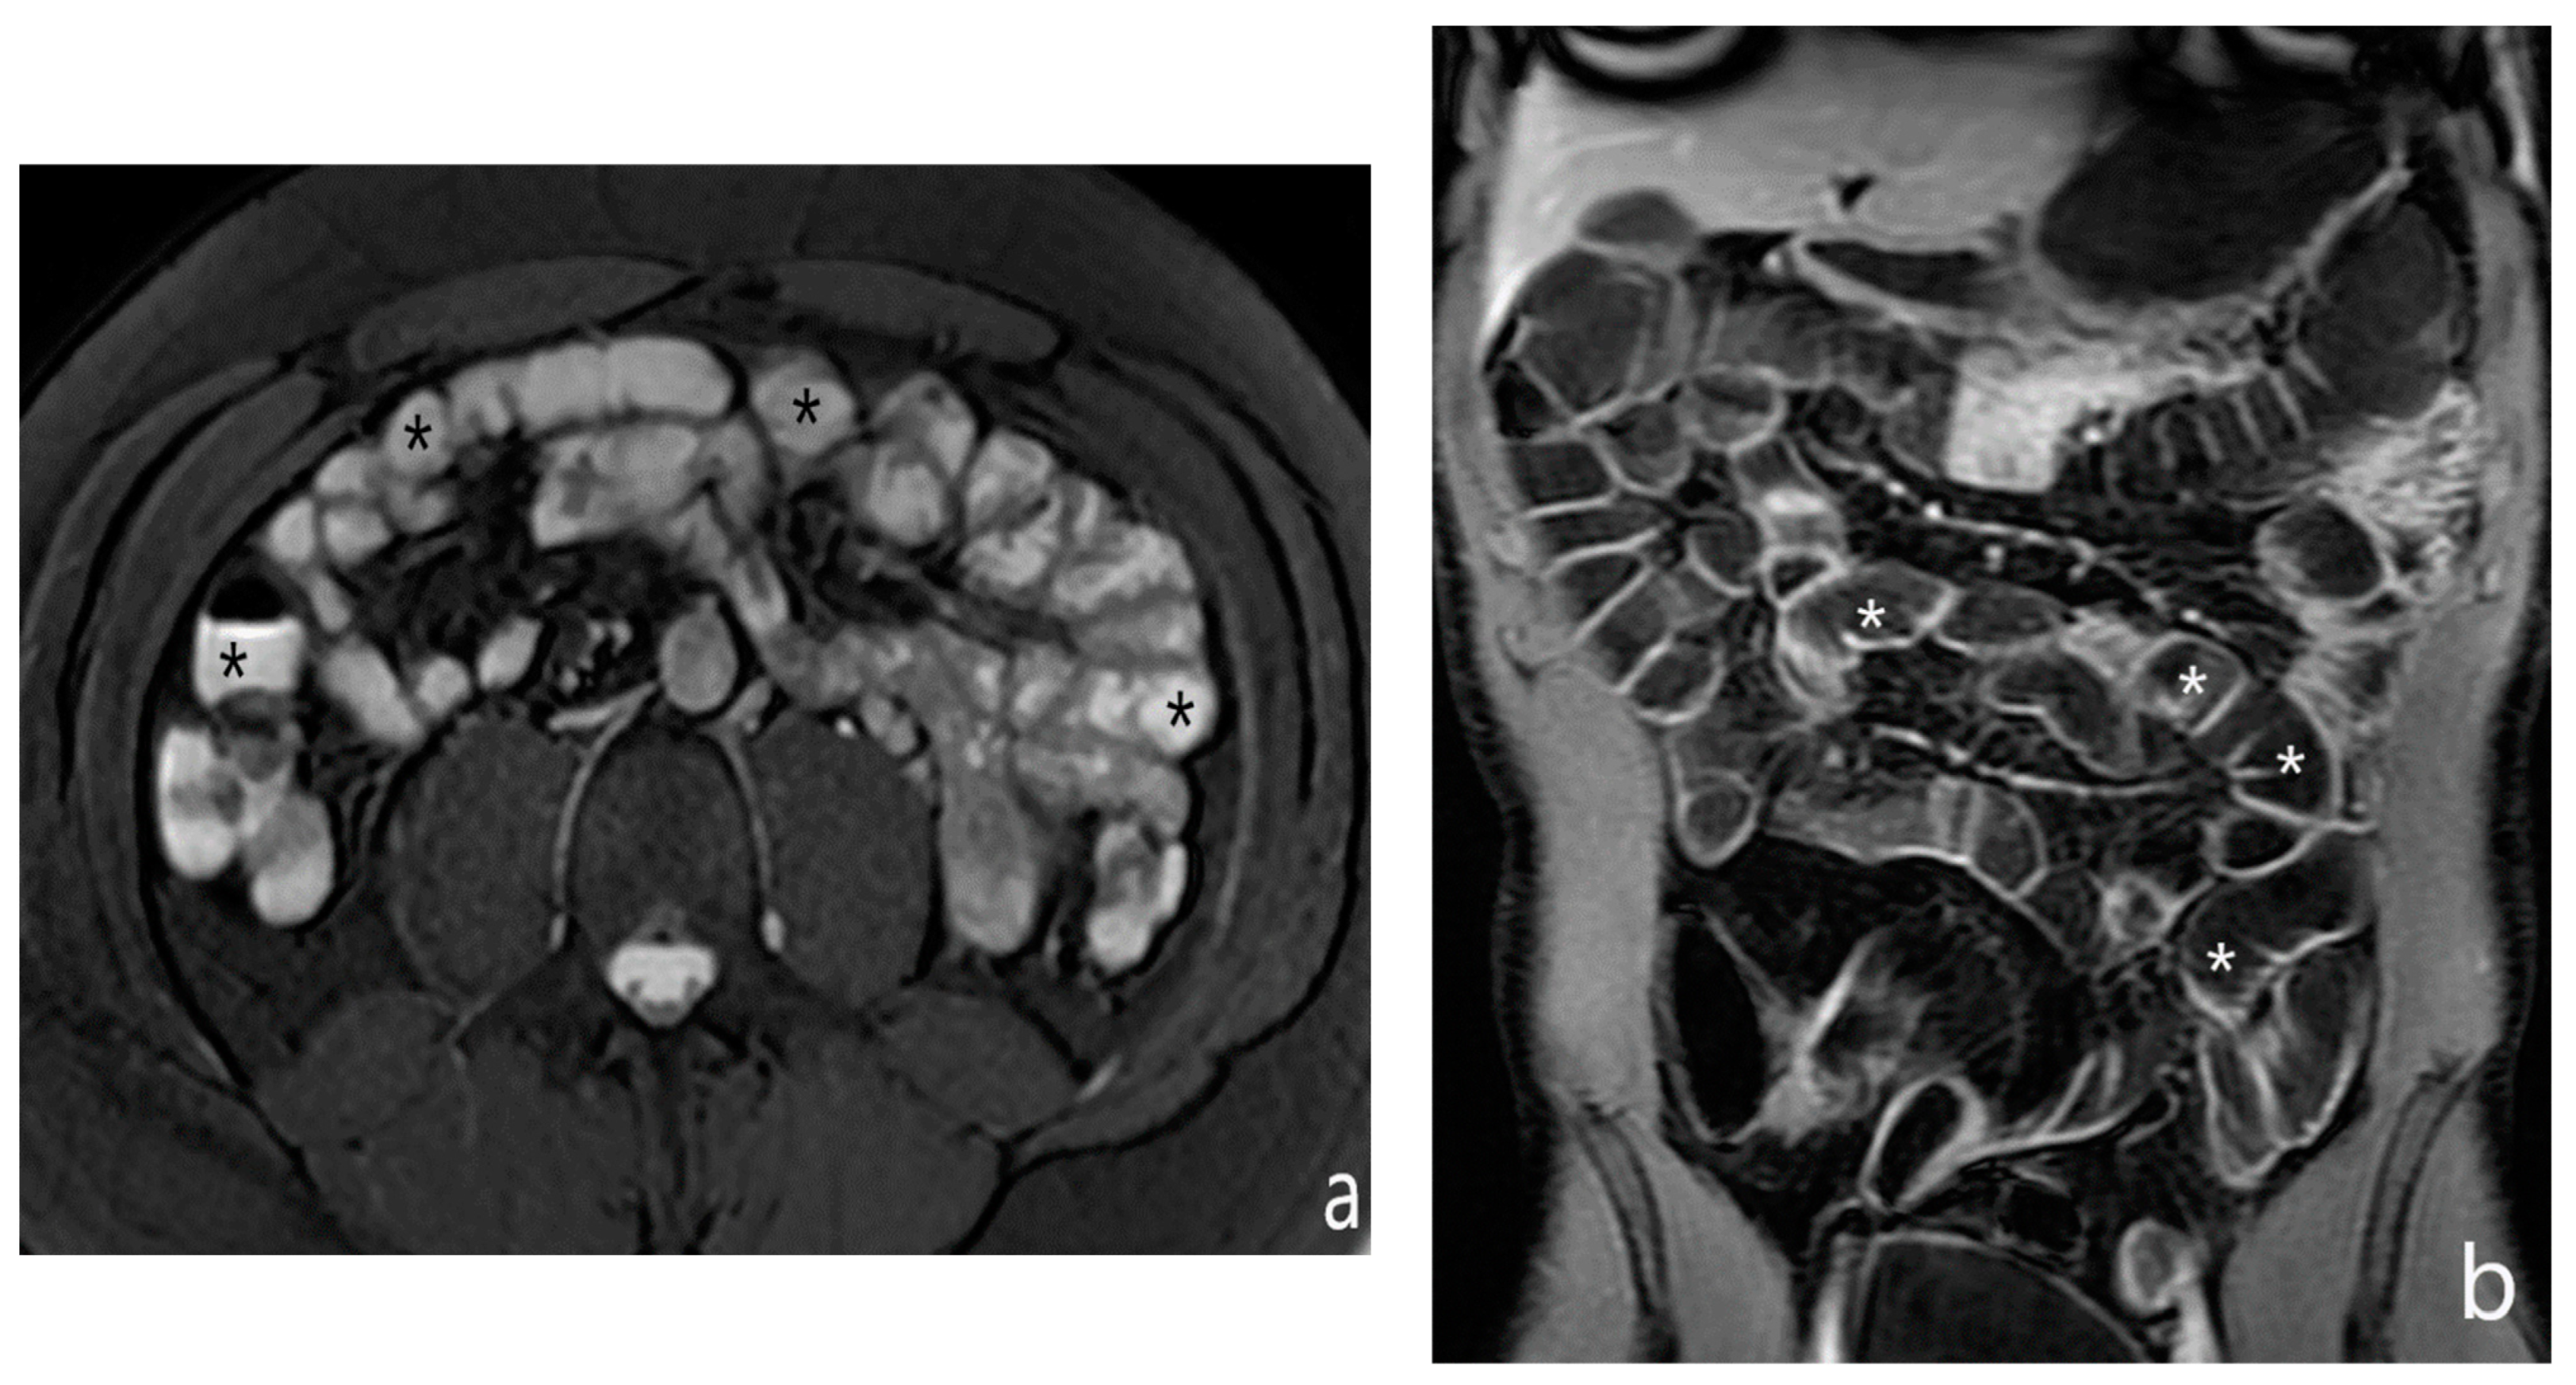

5.2. Fibro-Stenotic Subtype